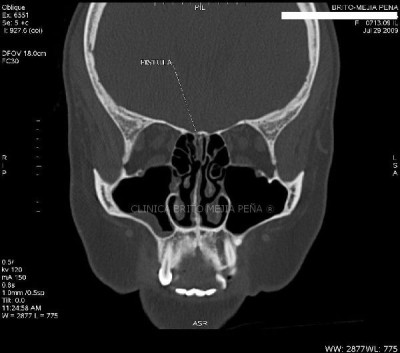

Fístula LCR axilar

Fístula LCR coronal